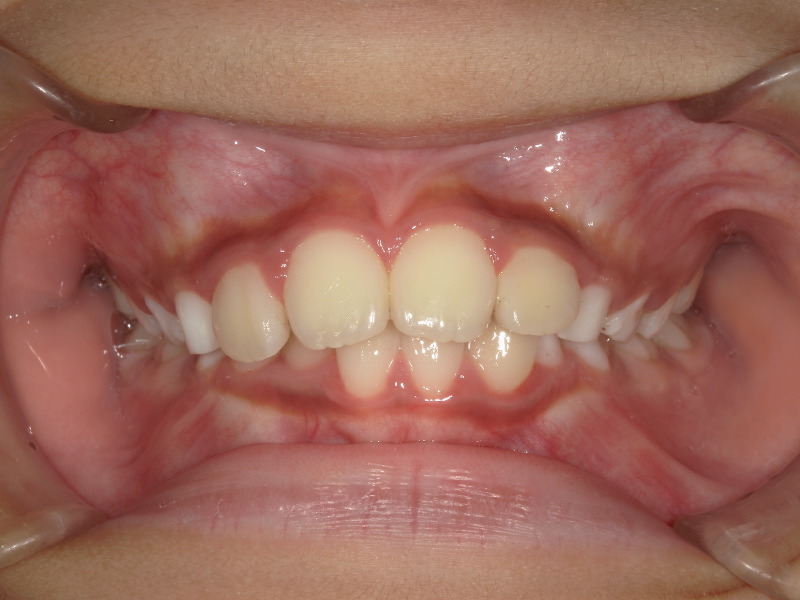

一年の経過

噛み合わせも少し変化があったり下の歯も並ぼうとはしていますがまだスペースは足りず入れませんでした。

3番目の歯が抜けて生え変わる頃にグッと噛み合わせが変化して、下の歯も並びました。

マウスピースとアクティビティーでここまで変化しました!

また、前歯が大きいと言われていたことが気になっていましたが顎も大きくなって正しく並んでいると大きく感じなくなります。